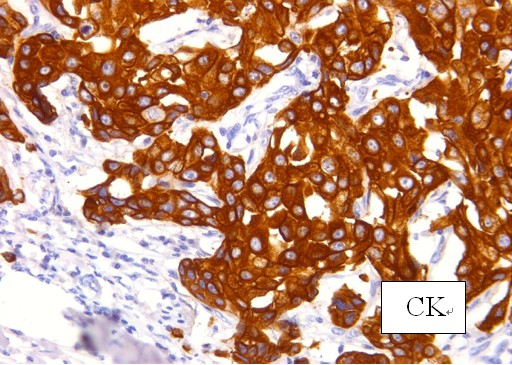

1. 密封瓶装、为微******透明液体基本无味。

8. 组织固定脱水系列套装试剂的免疫组织化学实验:免疫组织化学染色已经是肿瘤病理诊断和鉴别诊断的重要工具,该系列试剂的技术测试实验证明,经该系列试剂脱水包埋制备的组织切片用于临床病理诊断和鉴别诊断常用的几十种常用一线和二线抗体的免疫组织化学染色均能获得良好的染色结果。